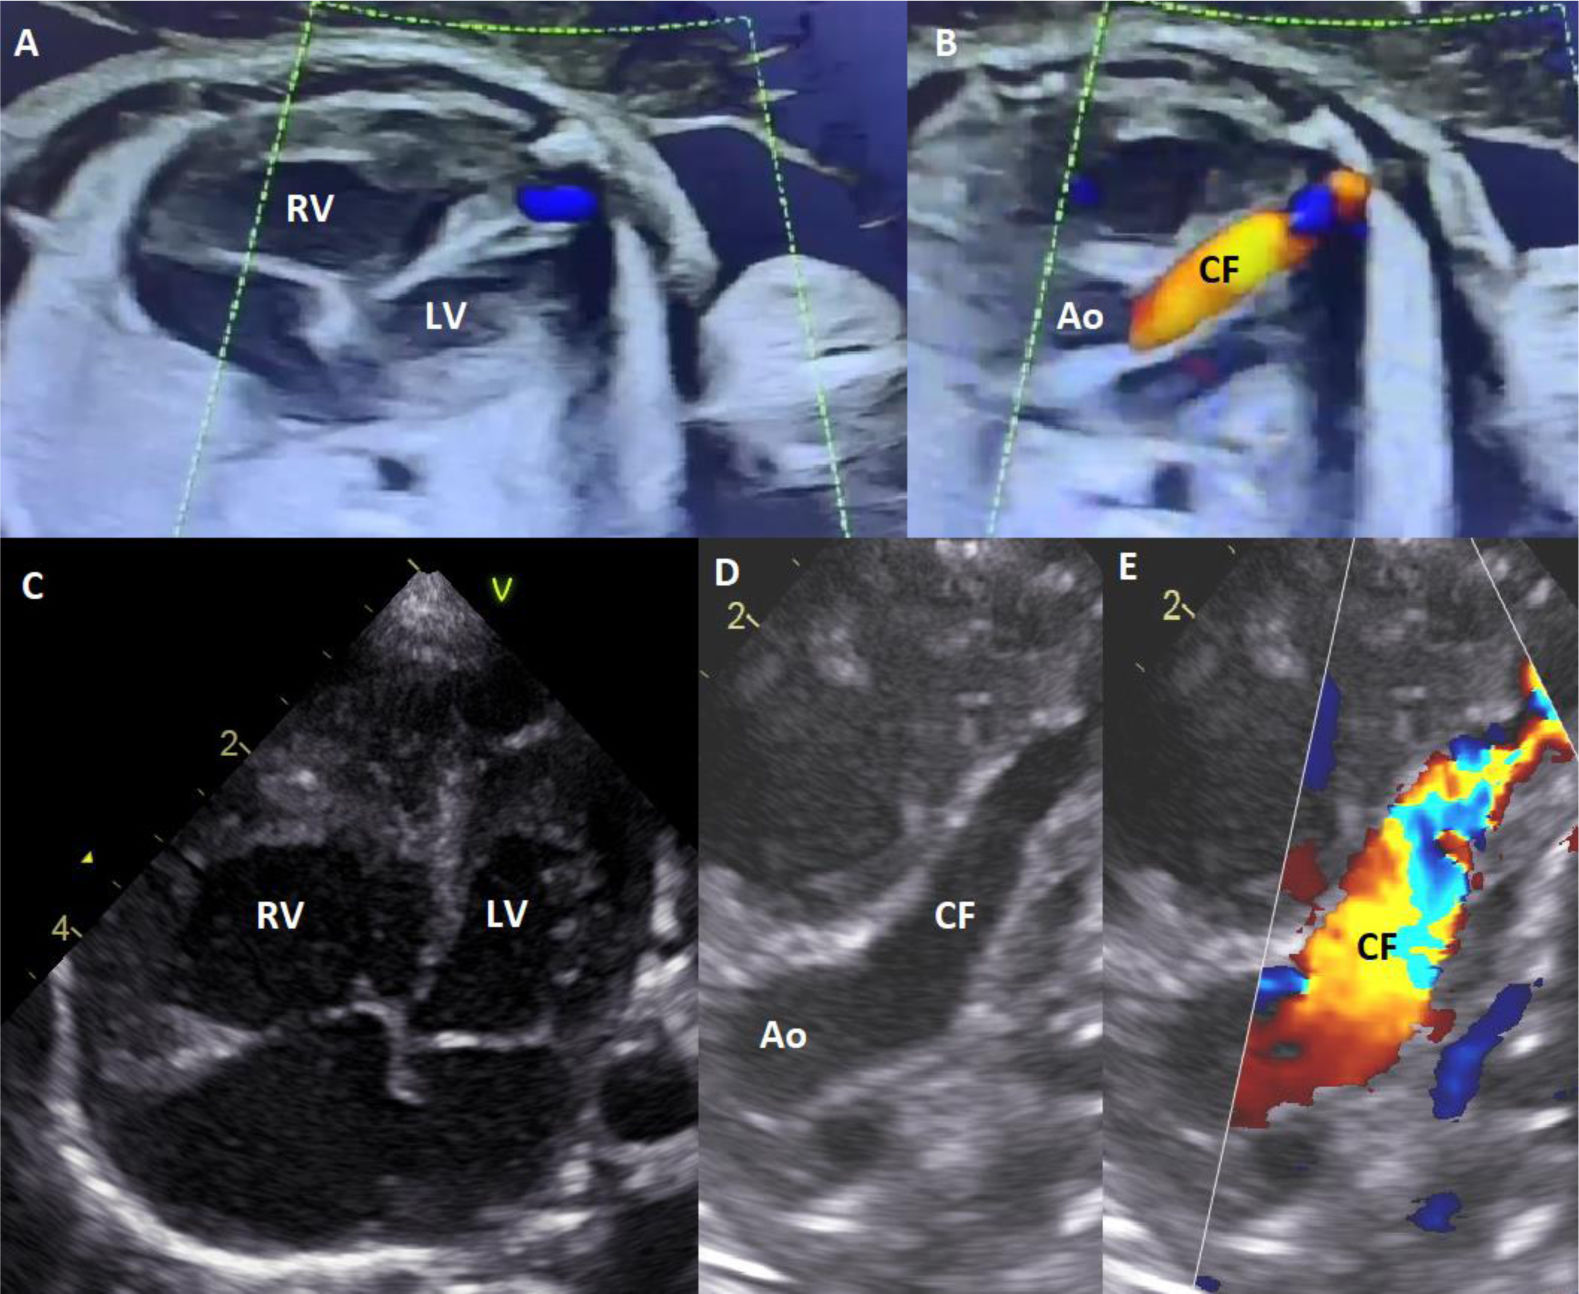

(A) Computed tomography angiography three-dimensional images showing the whole fistula to its distal end as it enters the right ventricular cavity (white arrow). (B) The same view from the surgeon's perspective. Multimodal evaluation allows for excellent preoperative assessment and adequately represents the anatomy the surgeon will find.

Echocardiography confirmed a large CAF with bidirectional flow and systemic diastolic steal. Computed tomogrpahy angiography (CTA) showed a large, tortuous vessel (8 mm × 7 mm at origin), distal diameter of 6 mm, with significant dilation of the right ventricle and atrium (Figure 2). Surgical ligation of the fistula was performed on day 3 (Figure 2). Persistent fistula on follow-up echo and CTA required re-ligation above the previous site on day 11, which resolved the condition. Both surgeries were uneventful, performed without extracorporeal circulation. The baby was discharged on day 17 with anticongestive therapy and is currently doing well, weighing 4600 g at 2 months.